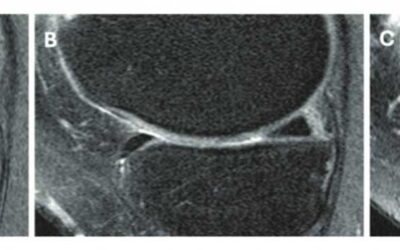

MRI vs SPECT-CT in Diagnosing Fracture-Related Talar Osteochondral Lesions

Ankle fractures are common, and although treatment is generally successful, up to 50% of patients experience long-term functional issues. One potential cause is the presence of hidden osteochondral talar lesions (OCTLs), which may not be easily detected with traditional imaging methods like MRI. While MRI is widely used, it often reveals OCTLs that are not related to symptoms, making clinical interpretation difficult.